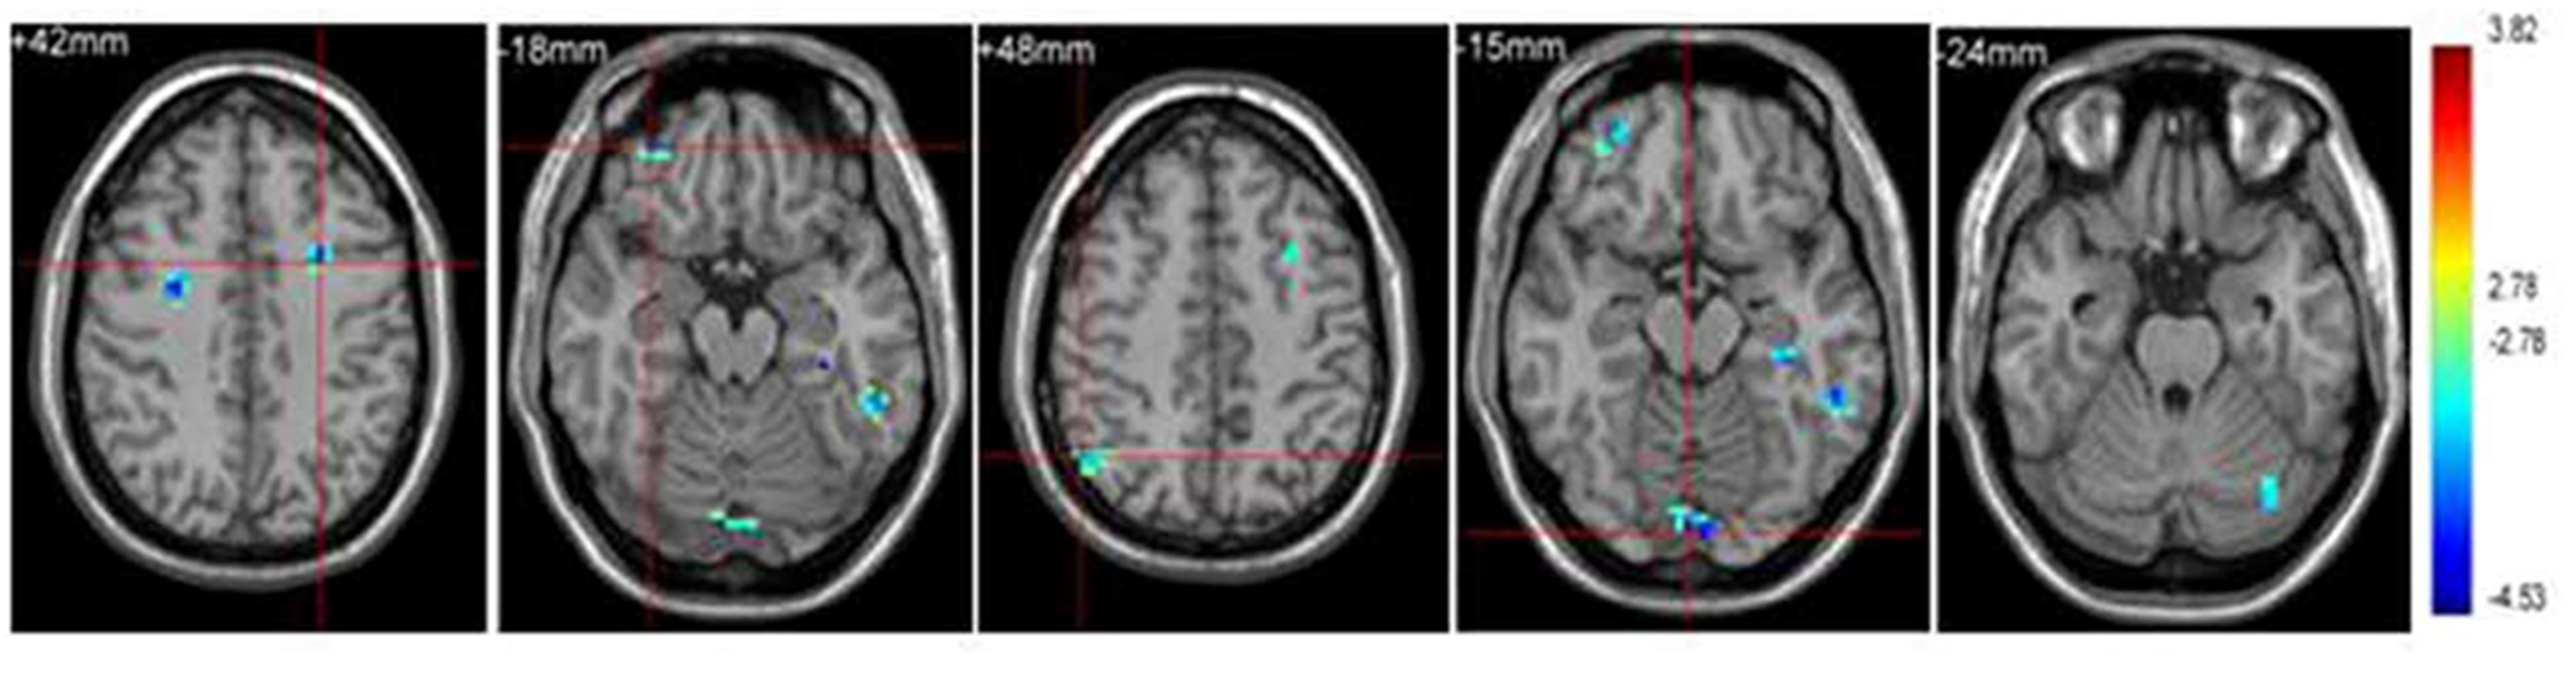

Figure 1.

Taekwondo group demonstrating enhanced functional connectivity (Reprinted with permission [19]).

In another study comprising aged subjects, an enhancement of cognition was observed in the aspects of attention, resilience and motor reaction time following a 5-month intervention with 89 older adults aged above 70 years. The main reason was attributed to the combination of aerobic, balance and coordination functions found in this East Asian martial art [52]. In another study, 1 h of weekly taekwondo training was provided to a group of 24 healthy volunteers aged above 40 years. The intervention lasted for a period of 4 months. It comprised the components of a warm-up, muscle strengthening and stretching, followed by taekwondo-based techniques. These components were aimed at improving stances, blocking, kicking, punching and the usage of kicking pads. All of them had shown improvement in reaction time and motor timing [53]. Taekwondo was analyzed for its efficiency in implementation in a public school setting. The executive functioning skills of the students who took part in taekwondo were higher than the control group. Computer administration was employed to assess executive functioning [54]. Around 30 healthy men volunteered to analyze the effects of the Japanese martial art kendo. Kendo practitioners demonstrated higher functional connectivity, mainly between the left intraparietal sulcus and left precentral gyrus [55]. The attention network test was performed on 48 participants of 2 groups, in which one had martial arts experience and the other did not. It was seen that all the martial artists had higher working memory, attention and behavioral inhibition. While this was more common among children, adults had improved corticospinal excitability resulting from karate and better motor cortex function from taekwondo. It was also seen that most benefits, especially among older adults, were due to chronic adaptations and not acute ones [56]. When analyzing the brain connectivity in children, taekwondo was proven to be effective in enhancing functional interconnection from the cerebellum to the inferior frontal gyrus. They also had enhanced minimal frequency oscillations in the right frontal precentral gyrus and right parietal precuneus. This resulted in enhanced intelligence [19].